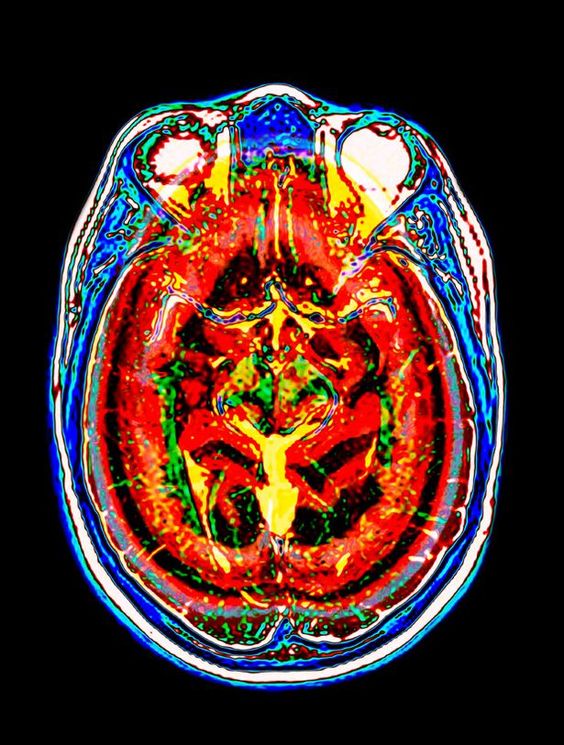

На сегодняшний день магнитно-резонансная томография (МРТ) головного мозга представляет собой превосходную альтернативу рентгенологическим методам исследования этого органа. Она имеет минимальное количество противопоказаний и позволяет получать высококачественные снимки, на которых четко видны изменения в тканях. Одним из значительных преимуществ является возможность получения изображений в цифровом формате, что делает МРТ незаменимым инструментом в случаях, когда требуется консультация нескольких специалистов.

МРТ основывается на явлении ядерного магнитного резонанса, которое заключается в изменении электромагнитного отклика ядер водорода при их возбуждении электромагнитными волнами в сильном постоянном магнитном поле. Поскольку водород присутствует во всех тканях организма, МРТ позволяет получать послойные снимки, из которых можно создать трехмерную модель исследуемого органа. Для улучшения качества изображения иногда вводится контрастное вещество через катетер или внутривенно.

В отличие от рентгеновских исследований, МРТ обладает высокой чувствительностью, что позволяет получать изображения мягких тканей без необходимости использования дополнительного оборудования и контрастных веществ. Эта особенность особенно полезна при диагностике заболеваний сосудов головного мозга и шеи.

Яркость изображения, получаемого при магнитно-резонансной томографии (МРТ) мозга, зависит не только от мощности используемого томографа. На снимках ярко выделяются участки, богатые жировыми клетками, поскольку они содержат больше атомов водорода. В результате костная ткань отображается в темных тонах.

Качественно выполненное МРТ мозга позволяет выявить нарушения кровообращения в этом органе, а также измерить пораженные участки при кровоизлияниях и травмах. Кроме того, оно помогает обнаружить изменения в структуре мозгового вещества, что делает его незаменимым инструментом в диагностике множества заболеваний.